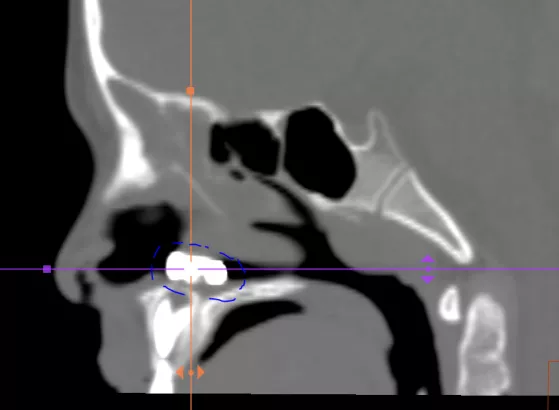

這名11個月的寶寶被撞後,當場昏迷,醫院檢查發現其顱骨骨折(圖中藍色區域)、顱內大面積出血,傷勢已經危及生命。

所幸經過神經外科醫生全力搶救,孩子的生命得以保住。